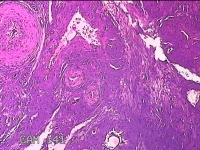

宫颈锥切物

性别

女

年龄

36岁

临床诊断

宫颈CIN2 宫颈乳头病毒感染

一般病史

检查发现CIN21个月。

标本名称

大体所见

灰白粉红色组织5.5x1.3x0.8cm一块,表面糜烂,切面灰白粉红色,质软,另有灰白粉红色组织2.3x2x0.3cm一堆,表面糜烂,切面灰白粉红色,质中。